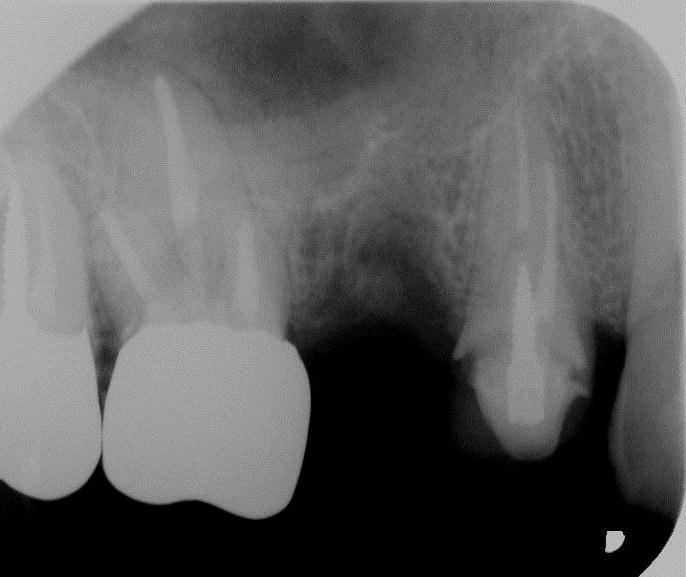

【審美歯科 前歯セラミック症例紹介②】

●治療箇所

左右2番目のは変色あり(歯の神経が死んだ状態)

●費用

セラミッククラウン

【オールセラミックe-max】

上記治療費用目安

初診検査 3500

グラスファイバーコア 10000×2本

仮歯 2本 2000×2本

歯型 5500

セラミッククラウン 69800×2本

調整装着費用 5500

治療回数目安 3回~6回

■ポイント■

前歯はオールセラミック(e-max,ジルコニアボンドセラミック)

が機能性・耐久性・審美性の面でゴールドスタンダード

オールセラミック 利点

金属アレルギーリスクがない

審美性 見た目が天然歯よりキレイ

歯ぐきが黒くなりにくい

オールセラミック 欠点

費用がある程度かかる

※上記費用は2020年現在のもの 最新費用はページ最上部をご覧ください